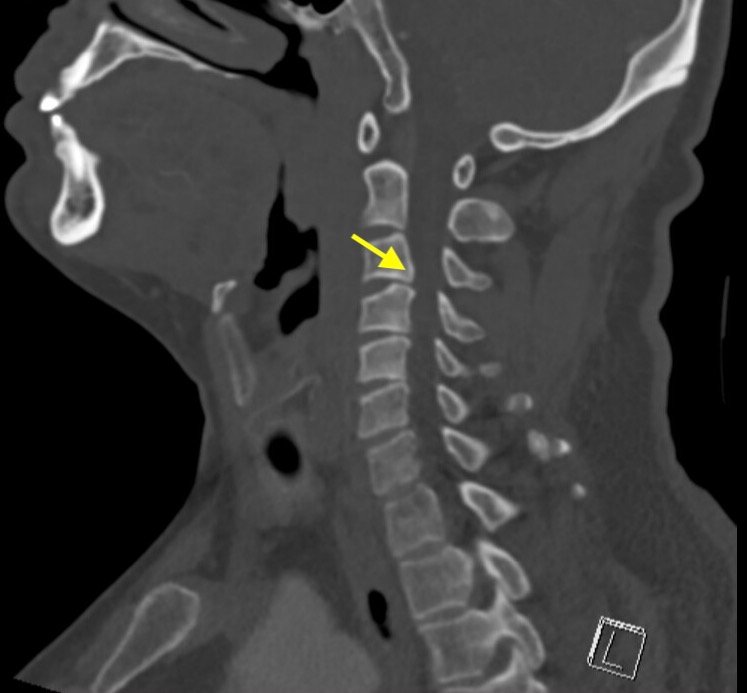

A 44-year-old male presented with sudden onset of severe left arm burning dysesthesia and bilateral leg numbness and weakness for several hours. He denied any recent illnesses or trauma and was previously healthy. His exam showed decreased strength to his left upper extremity, decreased light touch sensation to bilateral lower extremities, and urinary retention. Computed tomography (CT) and magnetic resonance imaging (MRI) of the cervical spine wereperformed, which demonstrated acute cervical myelopathy due to congenital cervical stenosis, a less common finding. Congenital cervical stenosis is the narrowing of the cervical spinal canal that is not due to structural, infectious,vascular, or malignant causes. This is an important diagnosis to consider in patients who present with neurologic symptoms without risk factors for common myelopathy causes (eg, degenerative changes). Early diagnosis and treatment are essential to prevent long term neurologic deficits.